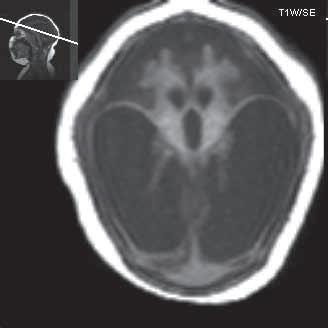

Obr. I.1.4a Lissencefalie typ I

Obr. I.1.4b Frontálně naznačená gyrifikace (šipka), kůra je nápadně tenká, vrstva bílé hmoty (přerušovaná šipka) odděluje mozkovou kůru od silné, vnitřní vrstvy šedé hmoty mozkové, lissencefalie typ I; stejný pacient jako na obr I 1 4a c d

Obr. I.1.4c Lissencefalie typ I

Obr. I.1.4d Lissencefalie typ I; stejný pacient jako na obr I 1 4c

Obr. I.1.4e Tenká mozková kůra (šipka), vrstva bílé hmoty (přerušovaná šipka), která odděluje kůru od silné subkortikální šedé hmoty (černá šipka), lissencefalie typ I

Obr. I.1.4f Tenká mozková kůra (šipka), vrstva bílé hmoty (přerušovaná šipka), která odděluje kůru od silné subkortikální šedé hmoty (černá šipka), lissencefalie typ I; stejný pacient jako na obr I 1 4e